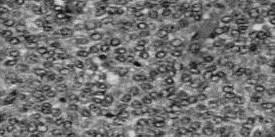

Ante la evidencia de un tumor inusual en la edad pediátrica se solicitó revisión de bloque celular e inmunohistoquímico cuyo resultado es el siguiente: hallazgos inmunohistoquímicos compatible con tumor de célula de la granulosa con área micro quística. Se confirma diagnóstico con una segunda revisión de bloque celular e inmunohistoquímico, que además reporta un índice mitótico elevado, con 7-8 mitosis atípicas por campo de 40 x (Figura 5). Se realiza gammagrama el cual reporta dentro de los límites normales, y perfil hormonal que incluyó α feto proteína (AFP), estradiol, progesterona, testosterona libre y testosterona total, todas dentro de los límites normales. Puesto que este tumor se comporta como tumor germinal.

Macroscópicamente se evidencia una masa quística amarillenta la cual está constituida histológicamente por células de la granulosa sola o en combinación con otras del estroma de los cordones sexuales y patrón de crecimiento difuso en macro-folículos (Figura 3, 4). Presentan morfología redonda u oval con abundante citoplasma y sin el típico núcleo en “grano de café” (con una hendidura atravesándolo) del TCG adulto (Figura 5); tampoco aparecen los cuerpos de Call-Exner (2,8,9). Estas peculiaridades sirven para el diagnóstico diferencial del TCG juvenil y adulto (Figura 5) y de los carcinomas indiferenciados ováricos, en ocasiones muy dificultosa (2).